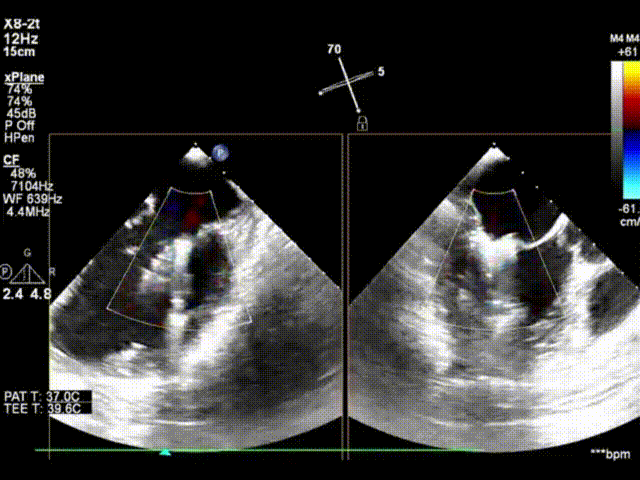

术前心超显示大量二尖瓣反流(反流宽度约1.8cm)

夹合后3D左房观,反流减少至轻微,跨瓣压差PGmax:6mmHg,PGmean:2mmHg